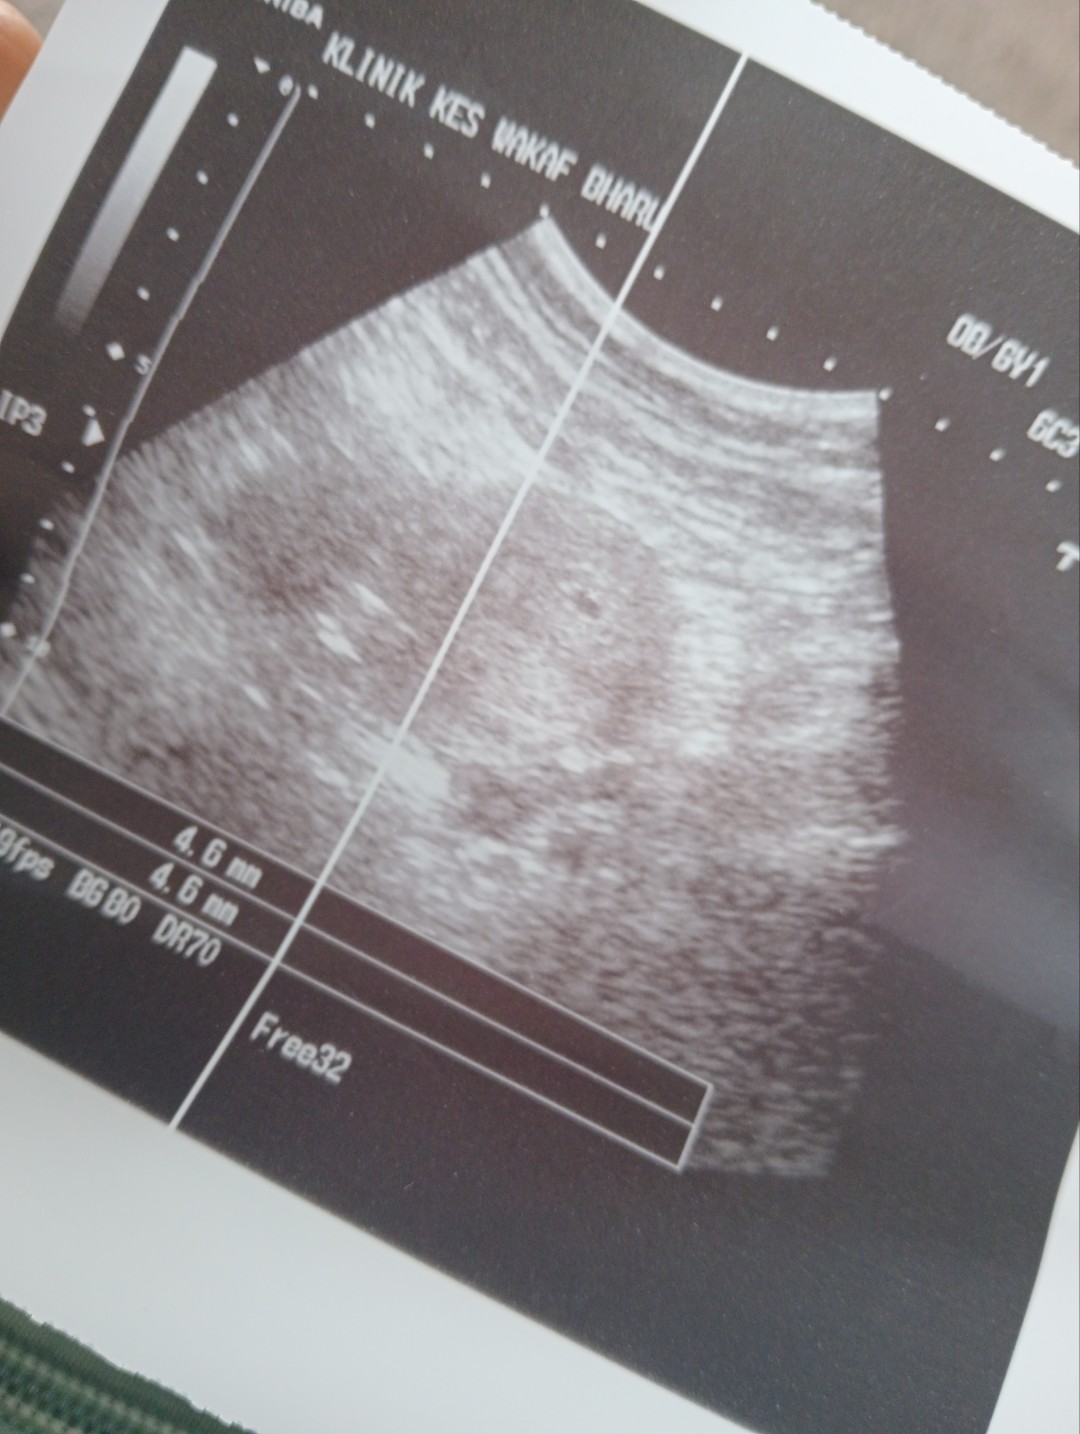

Upt positif tapi scan tak nampak kantung

24.4 Sy test upt kt RUMah 2x. Naik samar2 2 line. Terus Sy ke klinik swasta utk cek and scan . Tapi bila scan tak nampak kantung . Doc test HCG skli lg.. tetap naik double line. Sy kdg2 je rasa mual..xkuat. kdg2 pening.. tp kejap2 je.. mslh skrg Sy tkthu Sy preg btl ke x? Nk g scan tapi kena tnggu 2 mnggu lg. Lamaaa.. hati rasa rimas . Kepala serabut sbb xtau bby ada x. Blh tlg x ? Kalau g scan balik hrni rasa2 blh nmpk x